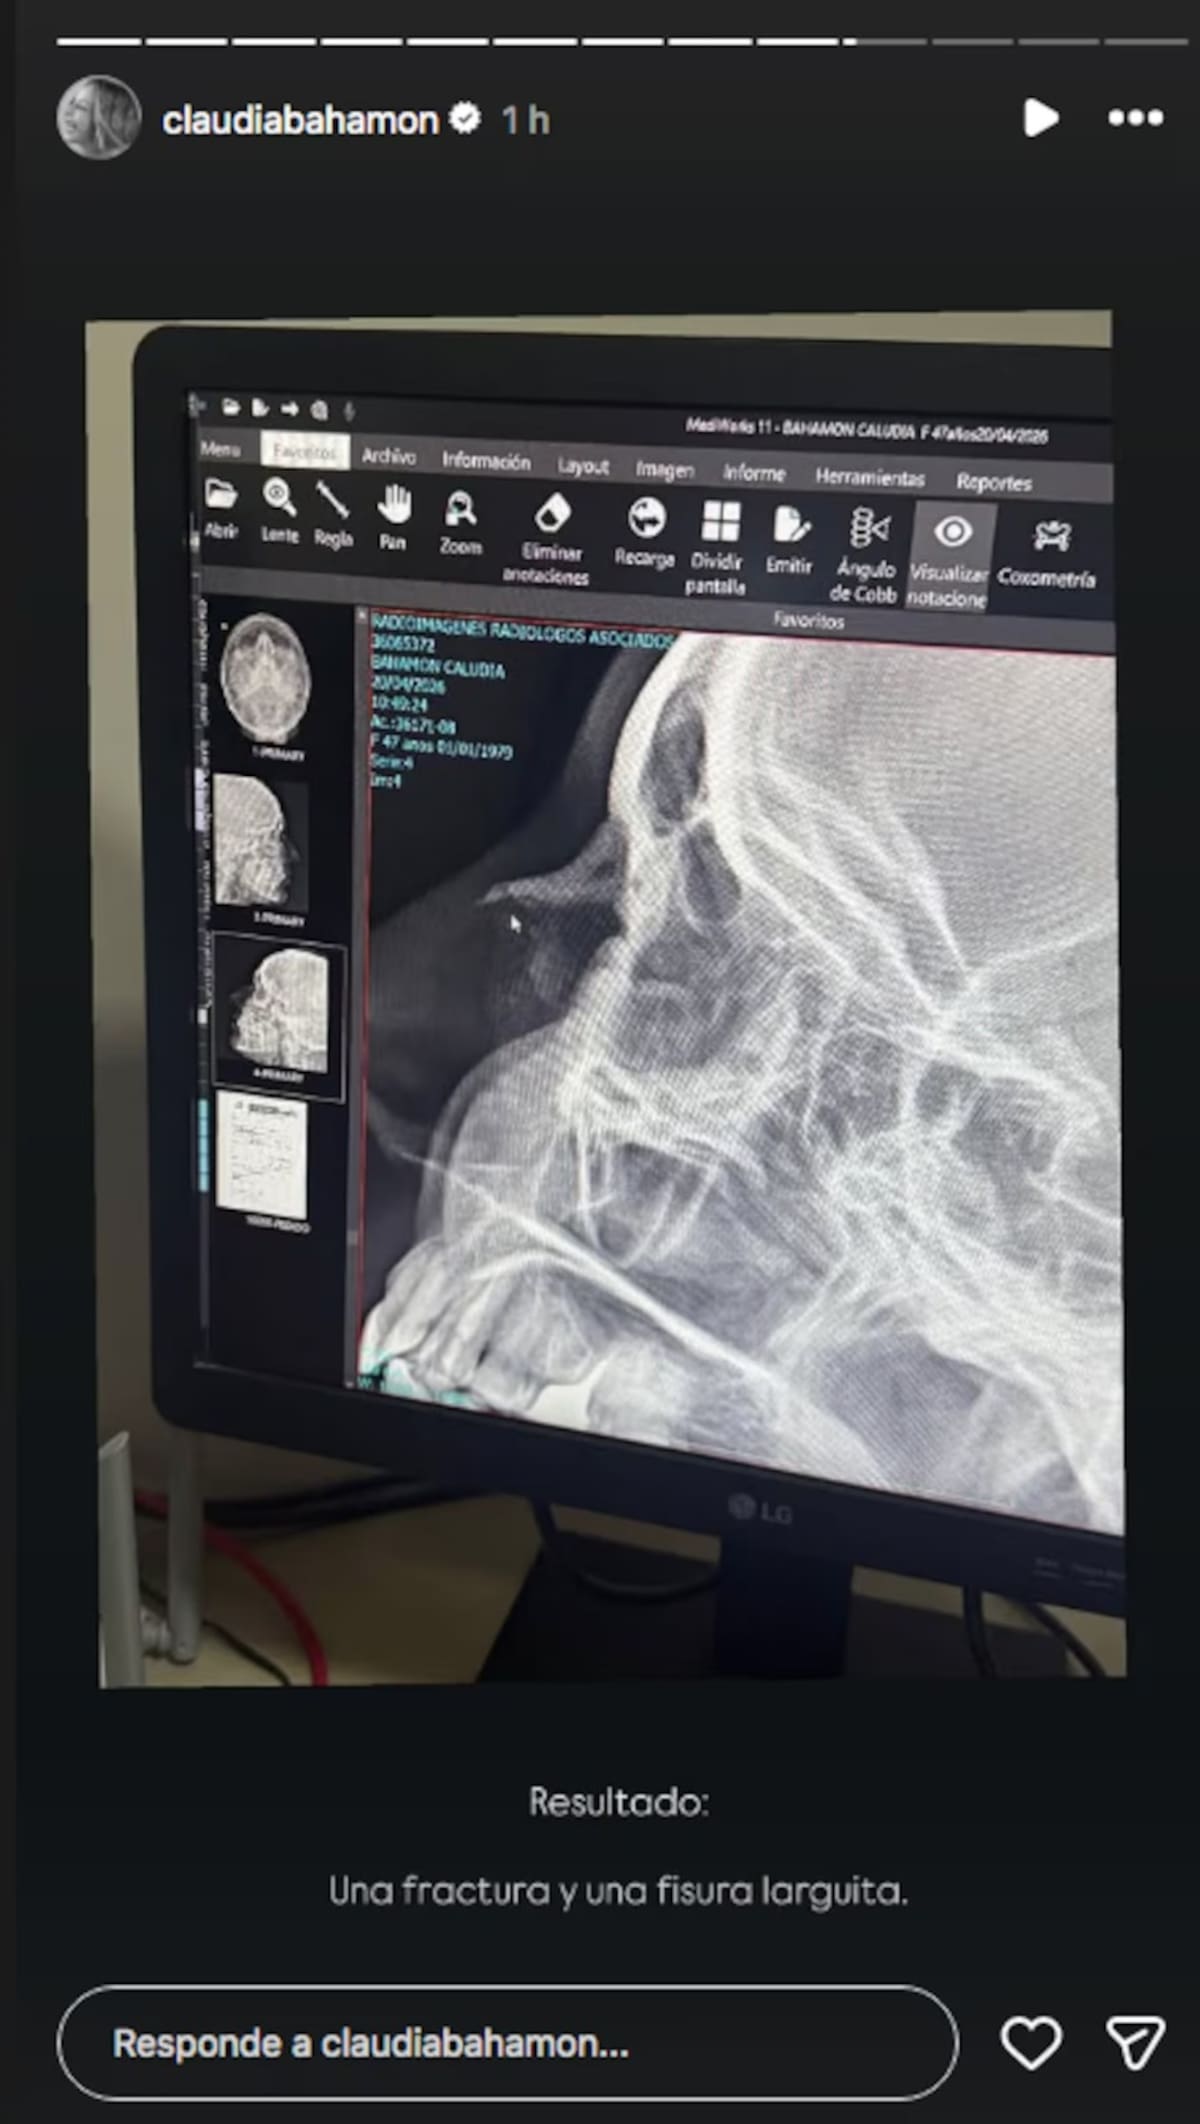

El resultado de los exámenes confirmó una fractura en la nariz y una fisura considerable, diagnóstico que generó preocupación entre sus seguidores.